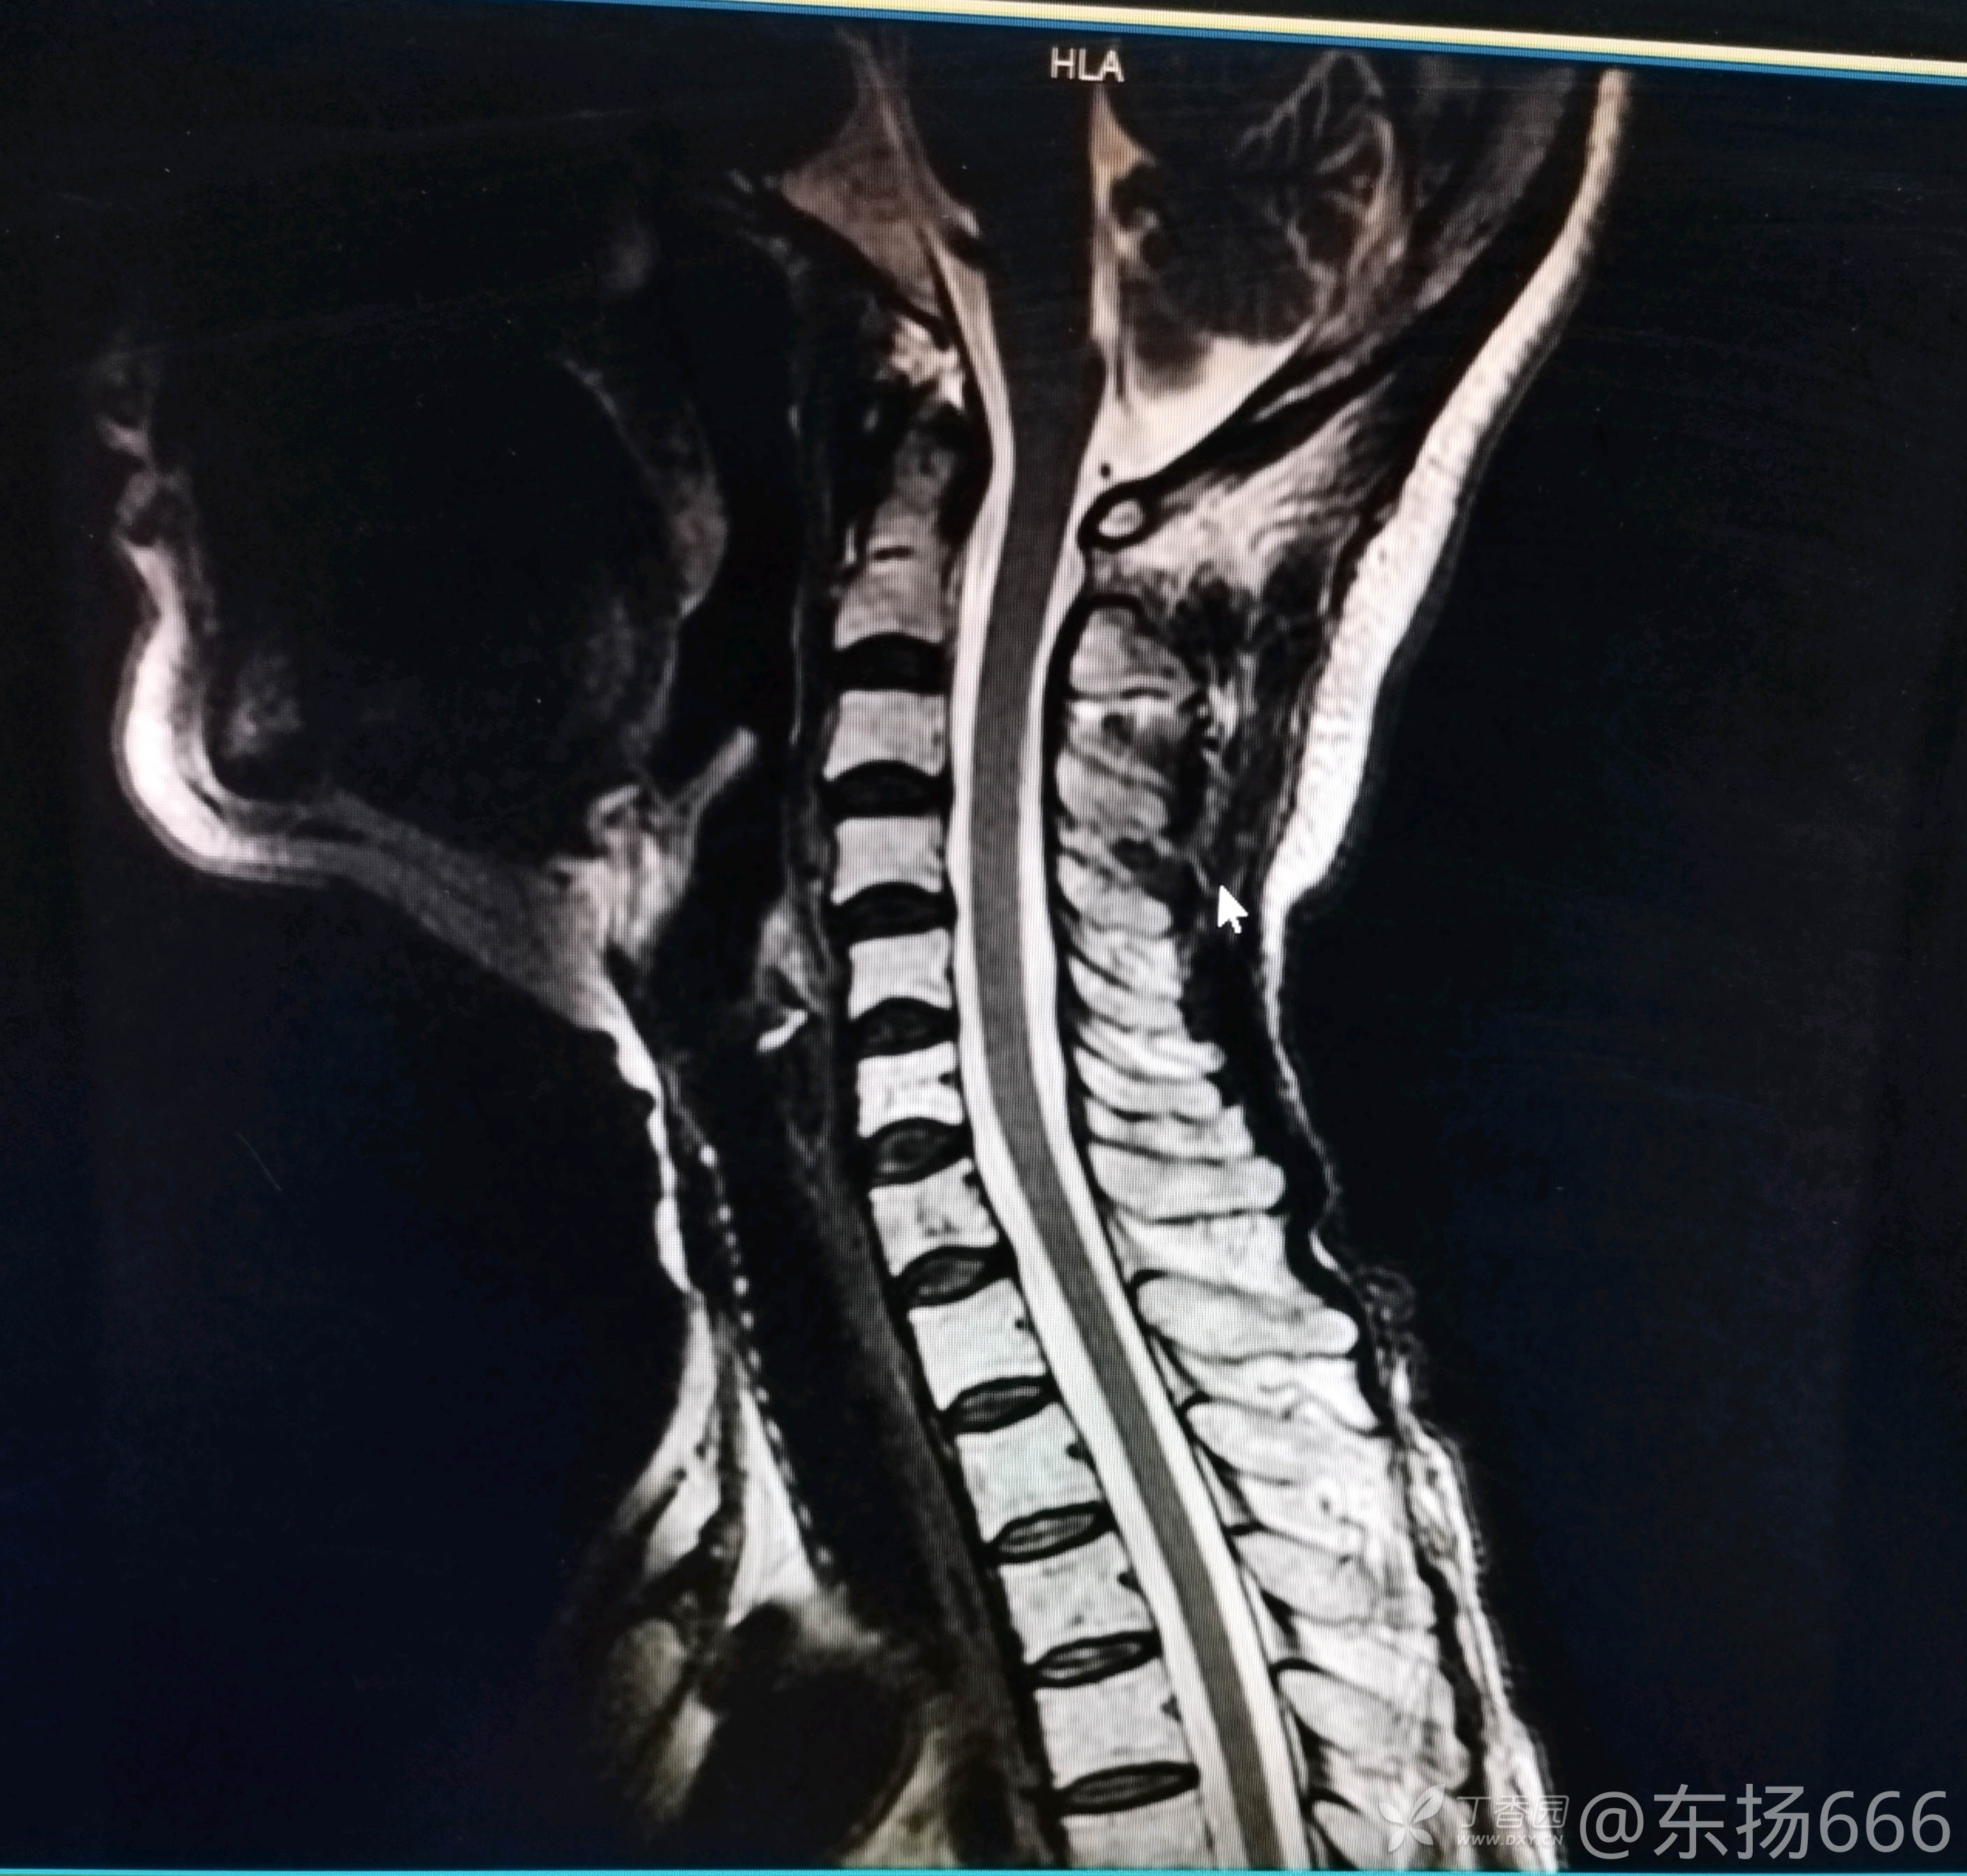

我院行颈椎MR示:颈椎间盘退行性病变。C2-7椎间盘突出